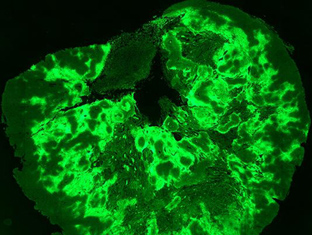

Illuminating tumour micro environments

Advanced technical imaging capabilities and research projects supported by MWC are helping to identify new prognostic and diagnostic biomarkers to advance potential therapeutic tar